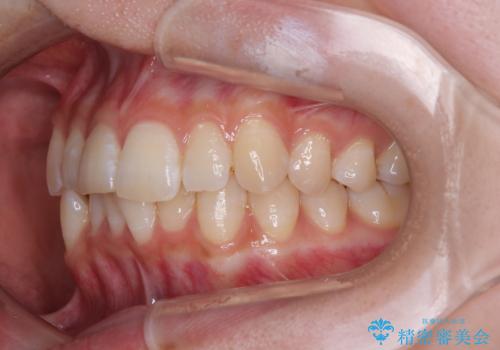

- 上下前歯の重なりを気にして来院された患者様です。

安価なインビザラインパッケージを用いての治療を希望されており、デコボコの程度が中等度であったため、インビザライン・モデレートを用いて矯正治療を行うこととしました。

インビザライン・モデレートは、製作できるアライナーの枚数に制限があるため、移動可能な量に限りがあるものの、インビザライン・ライトよりも枚数が多いため、幅広い症例に対応可能です。